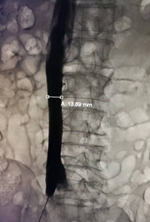

3. 41天濾器回收:

造影示下腔靜脈通暢,濾器形態(tài)居中,下方未見血栓形成。置入10F回收鞘,順利回收